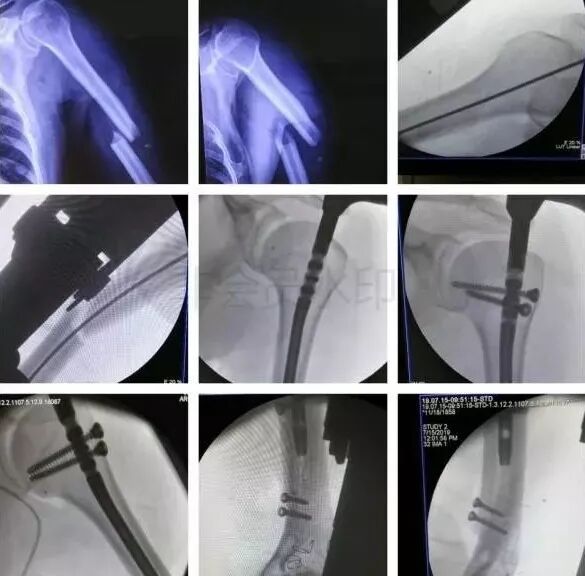

1)肱骨近端骨折

图片

脱位伤及腋神经、血管等,或者由于肱二头肌长头腱卡压无法复位,立即手术。

2)肱骨干骨折

• 合并桡神经损伤者,应立即手术。

• 常规手术应避免医源性损伤桡神经。

3)肱骨远端骨折

• 骨筋膜室综合征,立即减压。

• 前臂三大神经,肘血管损伤均可以探查。